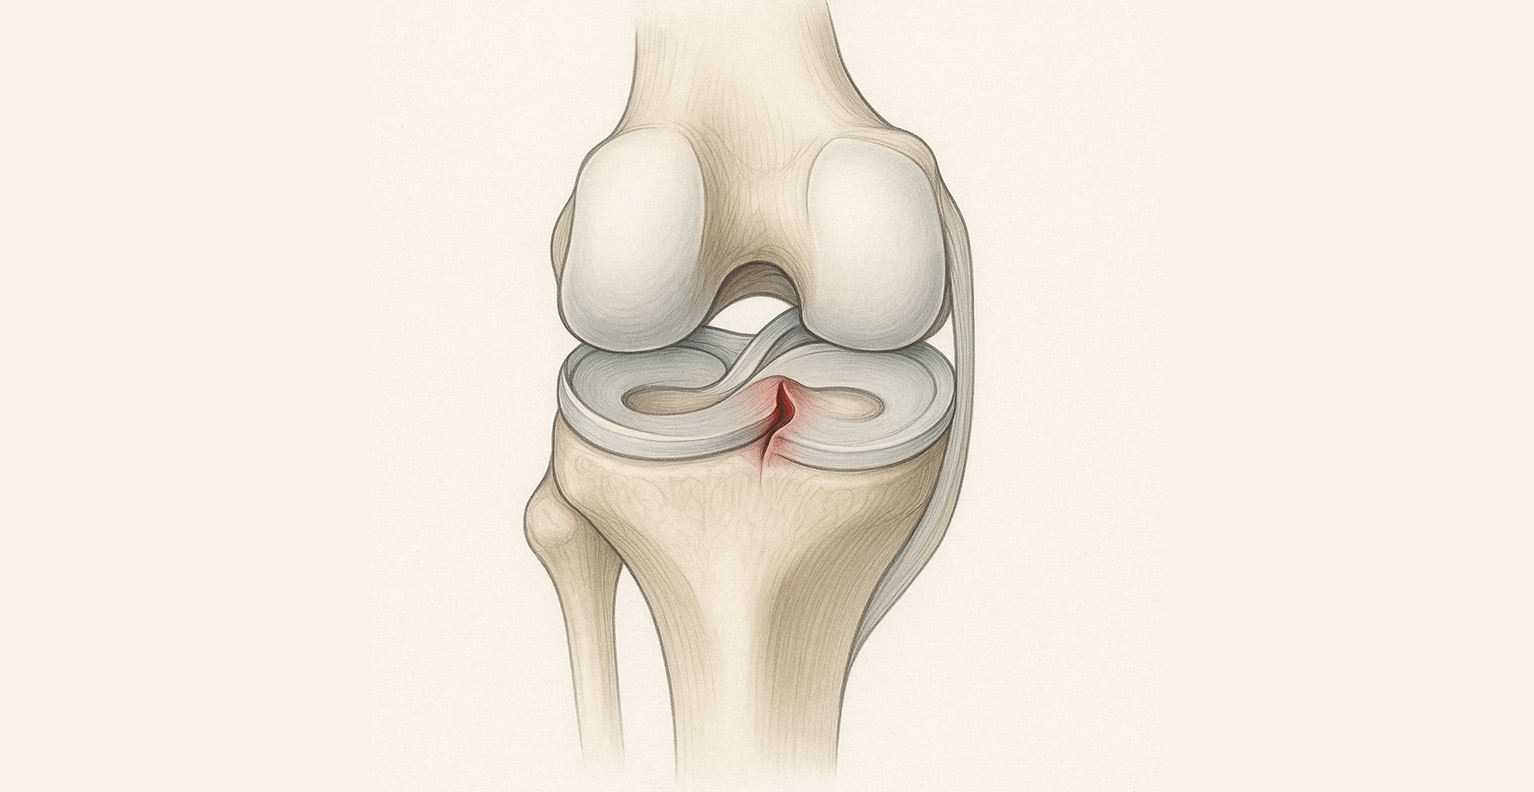

Bilimsel, Fizyolojik ve Osteopatik Bakış Açısıyla Menisküs Sağlığı

Menisküs, diz eklemimizin içinde yer alan ve şok emici, yük dağıtıcı ve eklemi koruyucu görevleri olan iki adet “yarım ay” şeklinde kıkırdak yapıdır.

Medial (iç) ve lateral (dış) olmak üzere iki tanedir.

Menisküsün dış bölgesi kanlanır, bu nedenle onarılabilir.

Ancak iç bölgesi damarsızdır ve bu yüzden kendini kolay yenileyemez.